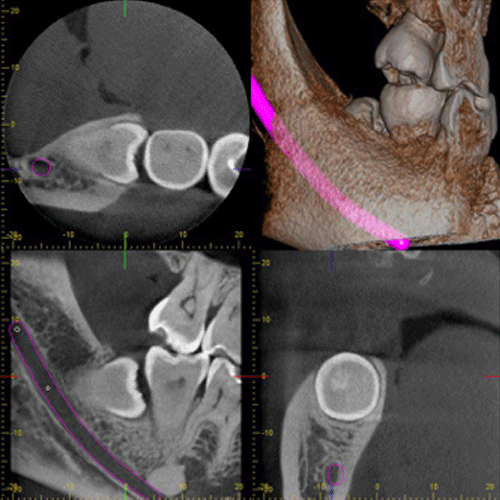

口腔外科治療とCT

親知らずや、埋伏歯の診断に利用することで、立体的に歯の位置や、顎骨の状態、周囲の神経や血管の管との関係を明確に診断できます。 それにより治療の安全性が高まり、患者様にとっても有益となります。のう胞や腫瘍に関しては、その位置や大きさなどを立体的に確認でき、その後の治療計画、処置に役立ちます。顎関節症、歯性上顎洞炎などの疾患に関しても、今までのレントゲンでは得られなかった情報を得れることで診査診断、治療に多く貢献できます。